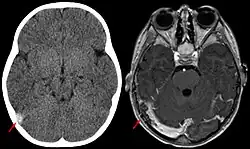

La trombosis del seno venoso cerebral (CVST) es la presencia de trombosis (coágulo sanguíneo) en el seno venoso dural, que recibe sangre de venas externas e internas del cerebro. Los síntomas de esta enfermedad pueden incluir dolor de cabeza, visión anormal, cualquiera de los síntomas de un accidente cerebrovascular (debilitamiento de los músculos de la cara y extremidades de una mitad del cuerpo) e infartos. El diagnóstico se realiza normalmente por tomografía axial computarizada (CT/CAT scan) o resonancia magnética (MRI) empleando el contraste radiológico para demostrar obstrucción de los senos venosos por trombos.[1]

Hay varias formas de neuroescaneo que pueden determinar la presencia de la trombosis del seno venoso cerebral. Los edemas cerebrales e infartos venosos pueden hacerse visibles en cualquier modalidad, pero para la detección del trombo sí, el tipo de escaneo más usado comúnmente son la tomografía axial computarizada (CT) y la resonancia magnética (MRI). Ambas usan varios medios de radiocontraste para elaborar un venograma y visualizar las venas en torno al cerebro.[1]

La tomografía axial computarizada tiene una capacidad de detección que para algunos expertos supera la de la resonancia magnética. Esta prueba se basa en la inserción, a través de una inyección en la vena (normalmente en el brazo), de una sustancia radiopaca. Tras un tiempo, el que tarda el torrente sanguíneo en llevar la sustancia al cerebro, el escaneo se realiza. La sensibilidad de este test es de 75-100% (detecta de 75 a 100% de todos los coágulos presentes), y una especificidad de 81-100% (sería incorrectamente positivo en un 0-19%).[6]

La resonancia magnética venosa emplea los mismos principios, pero la modalidad de escaneo usada es la resonancia magnética. La MRI tiene la ventaja de ser mejor a la hora de detectar peligro para el cerebro como resultado del incremento de la presión en las venas obstruidas. No obstante, este mecanismo no se encuentra disponible en muchos hospitales y su interpretación puede resultar dificultosa.[6]